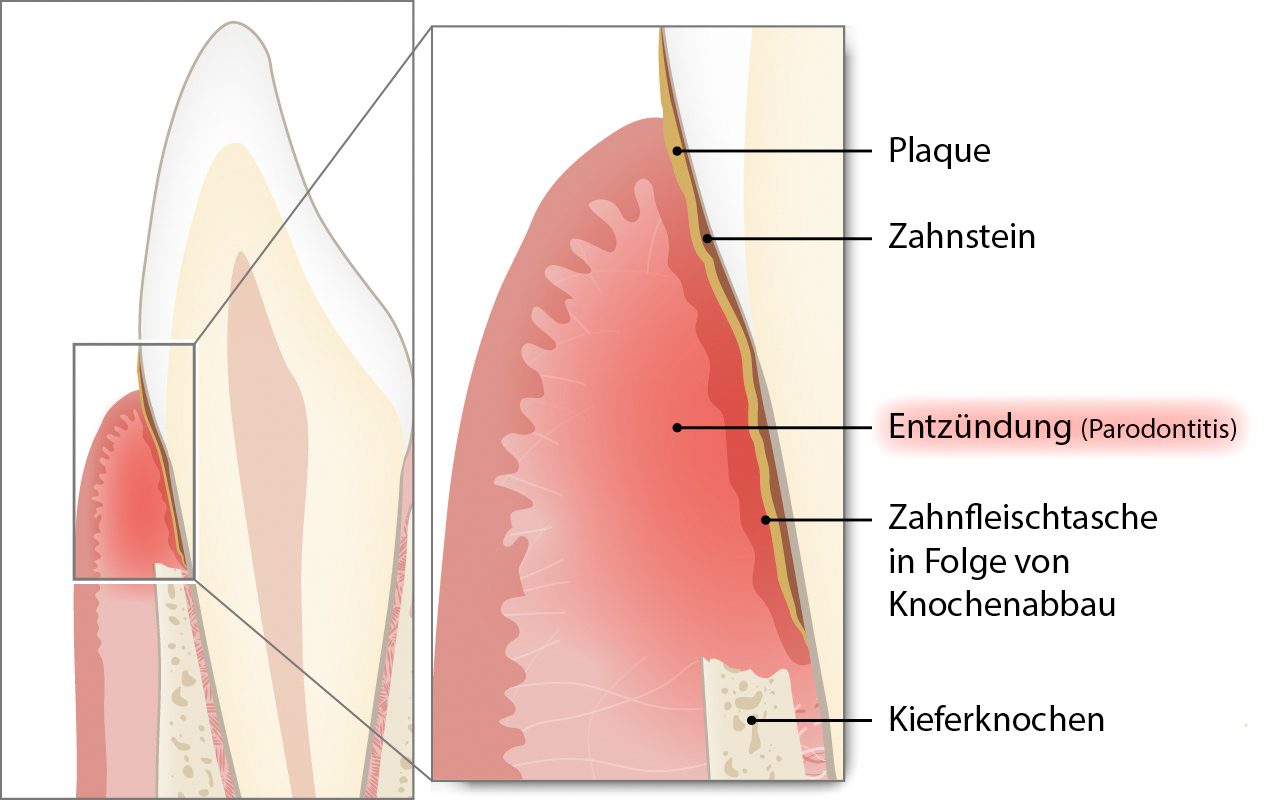

Mehr ...Parodontitis gehört zu den häufigsten chronischen Krankheiten des Menschen. Es handelt sich um eine entzündliche Erkrankung, die alle Teile der Zahnverankerung betrifft.

Was ist die Parodontitis und wie häufig kommt sie vor?

Parodontitis gehört zu den häufigsten chronischen Krankheiten des Menschen. Es handelt sich um eine entzündliche Erkrankung, die alle Teile der Zahnverankerung betrifft.

Als Folge der Entzündung des Zahnfleischrandes (Gingivitis) kann es zum Abbau der Verankerungsfasern und des Kieferknochens kommen. An Stelle des gesunden Faserapparates entsteht entlang des Zahnes eine sogenannte Zahnfleischtasche. Die dort liegende Wurzeloberfläche ist mit bakteriellen Belägen (Plaque und Zahnstein) bedeckt.

Der Abbau der Verankerungsfasern und des Kieferknochens kann zu einer erhöhten Zahnbeweglichkeit führen. Falls die Erkrankung unerkannt bleibt und nicht behandelt wird, kann sich der Abbau soweit fortsetzen, dass die Zähne in ihrer Funktion zum Kauen unbrauchbar werden und gezogen (extrahiert) werden müssen.

Rund 40 Prozent der Menschheit leiden an Parodontitis. Für die Erwachsenenbevölkerung wird geschätzt, dass heute rund 70% des Zahnverlustes auf die Parodontitis zurückzuführen ist.

Erfahren Sie mehr über die Ursachen, Folgen, Diagnose, Therapie und Vorbeugung der Parodontitis unter: www.parodont.ch.